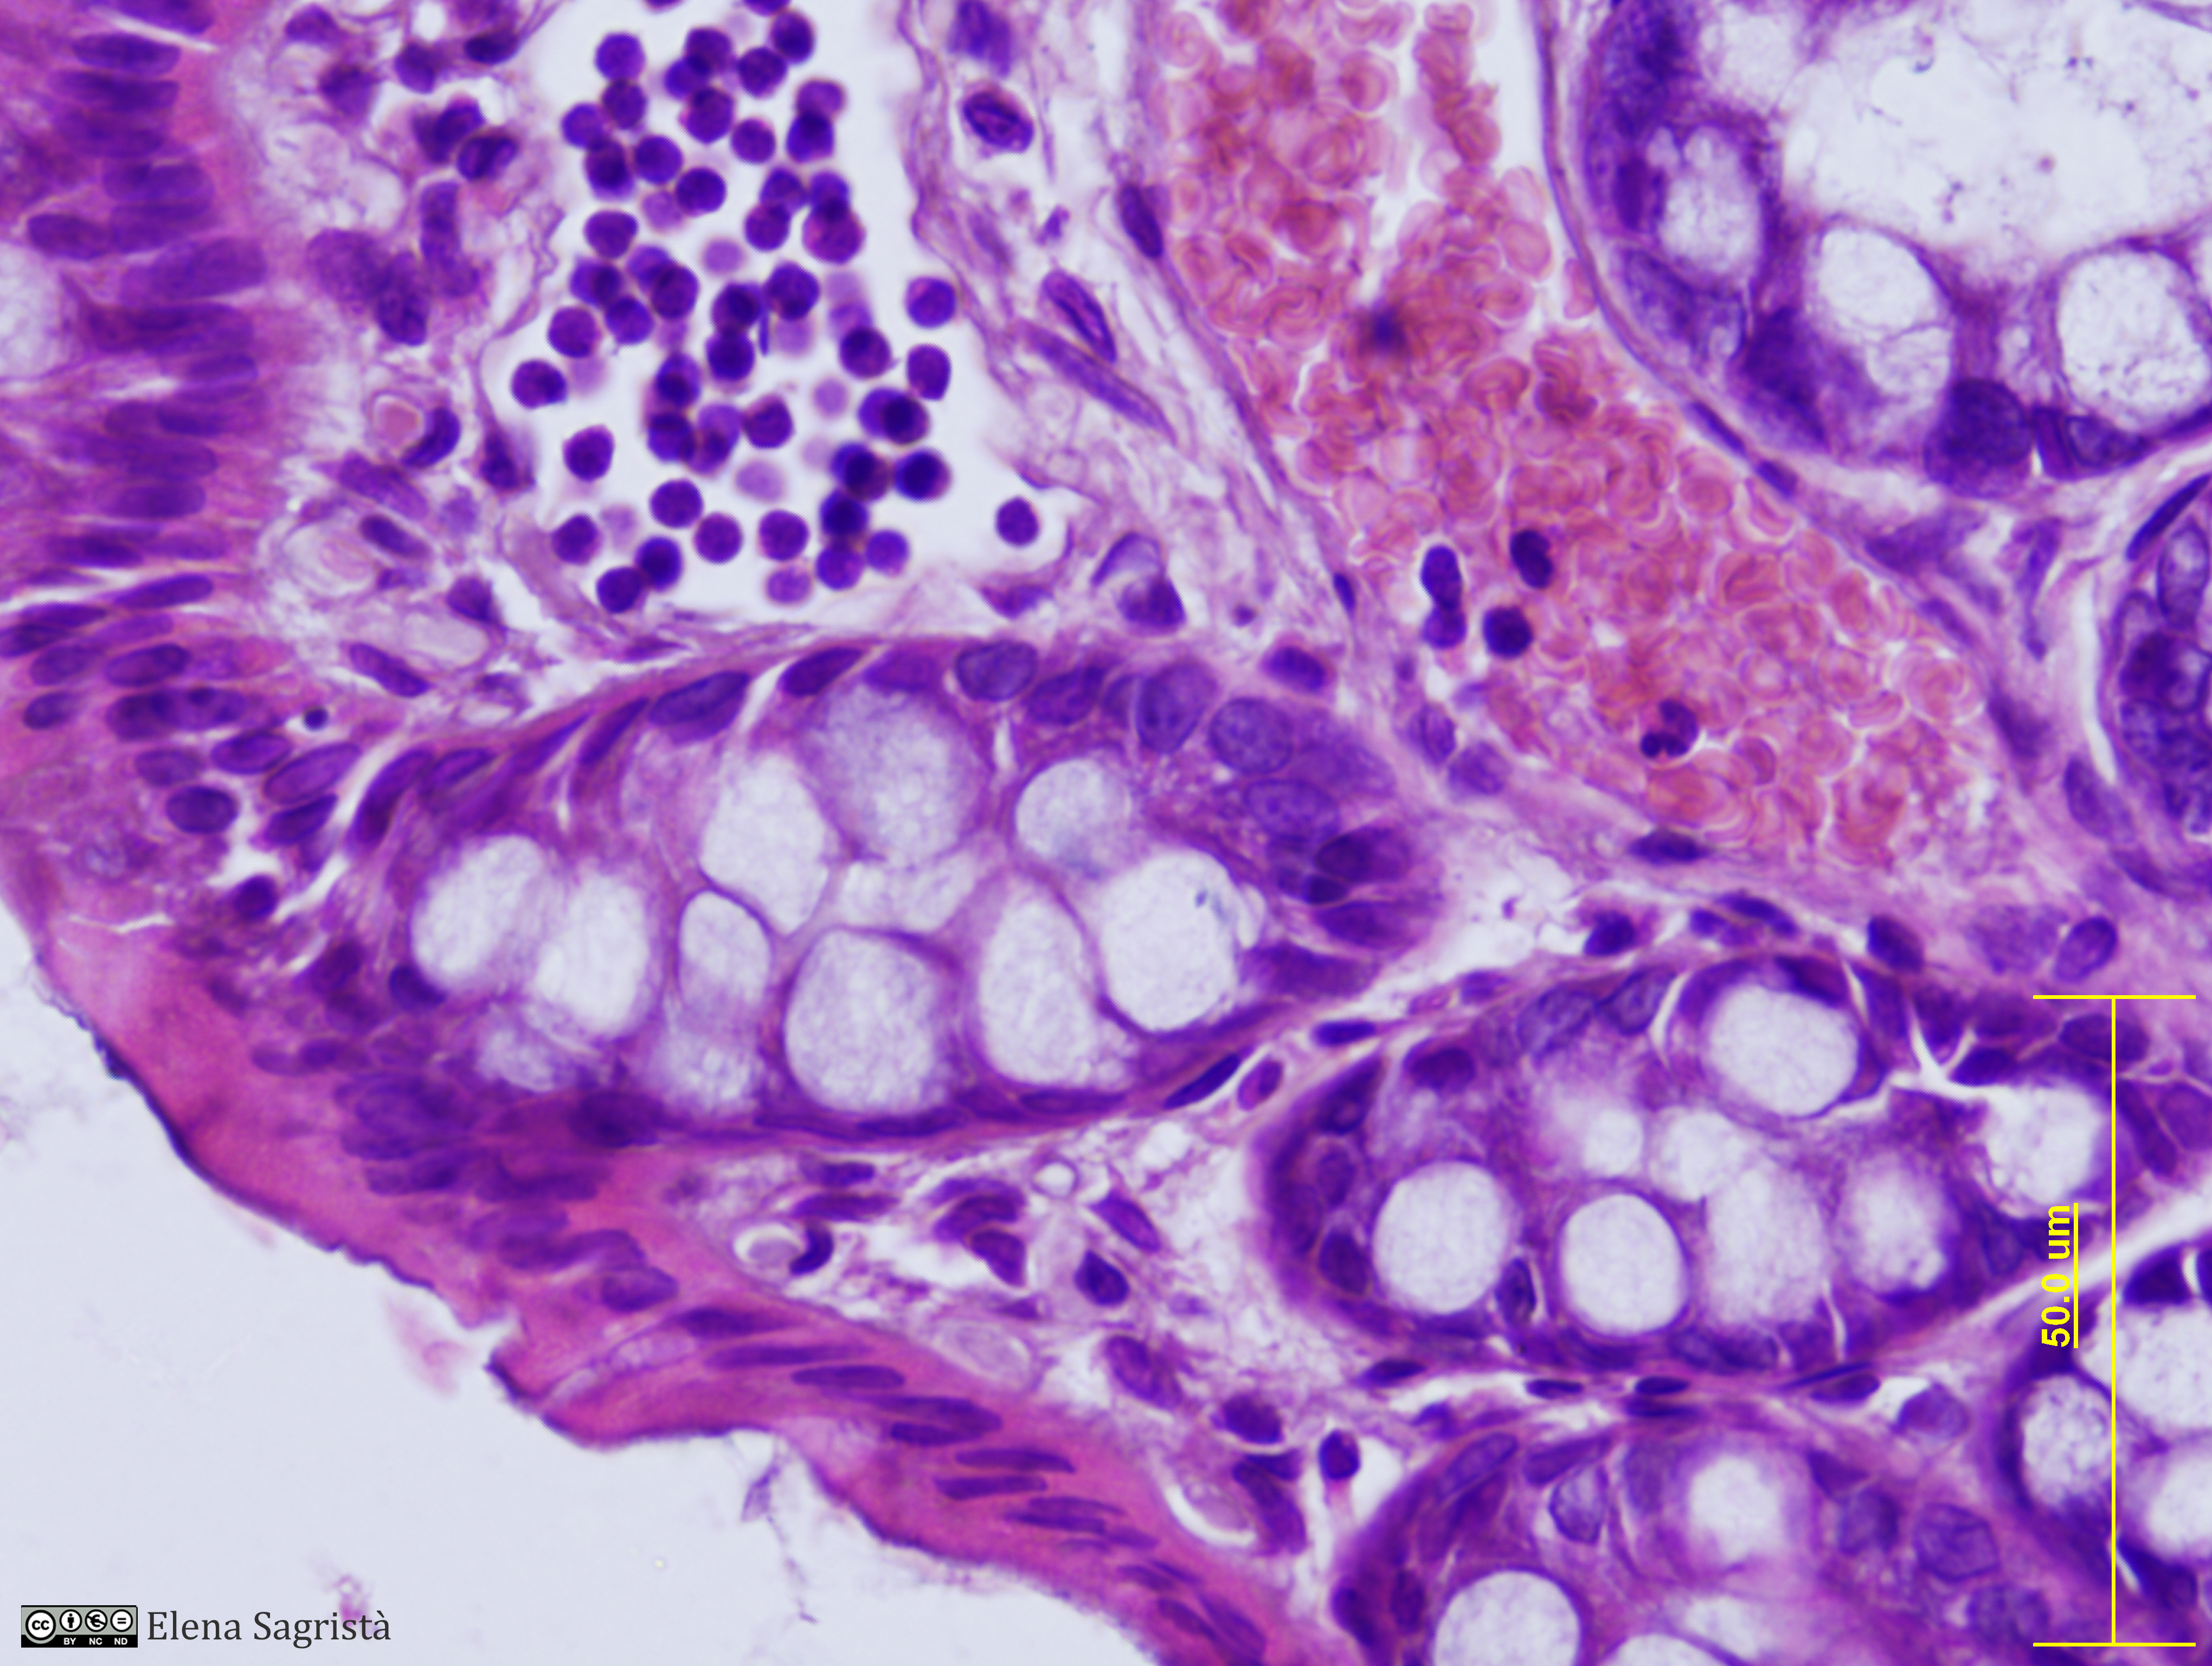

Histologia imatges: 10 Vasos sanguinis i limfàtics

Imatges de preparacions histològiques de Vasos sanguinis i limfàtics. Microscopia òptica.